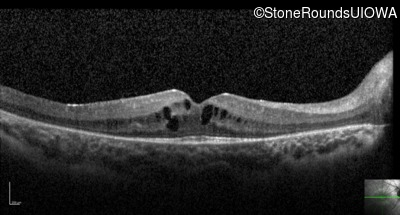

Visit at age: 21 years

Optical Coherence Tomography - Left - 20/32

Exemplar / OCT Stack